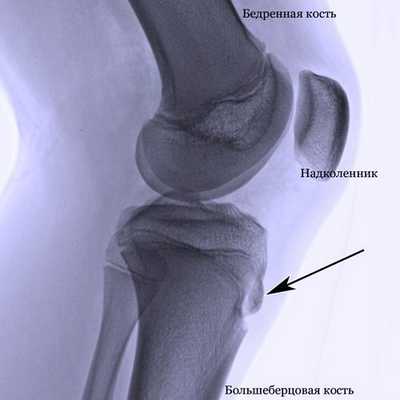

Для постановки окончательного диагноза рекомендовано рентгеновское исследование: выполняют снимок в прямой и боковой проекции.

Рентгенологические исследования суставов предназначены для поиска травм и других патологических изменений.

Решающим фактором в вынесении однозначного диагноза болезнь Осгуда-Шлаттера у детей и подростков была и остается рентгенография, которую с целью повышения информативности течения патологии лучше всего проводить в динамике. Для исключения прочих ортопедических заболеваний подобное обследование пораженного коленного сустава необходимо осуществлять в двух проекциях, а именно в боковой и прямой.

В начальной фазе развития заболевания на рентгенологических снимках отмечается уплощение бугристости большеберцовой кости в ее мягкой части и подъем нижнего края просветления, отвечающего расположенной в передней доле коленного сустава жировой ткани. Последнее несоответствие норме вызвано увеличением размера поднадколенниковой сумки, происходящее вследствие ее асептического воспаления. Какие-либо видимые изменения в самом ядре окостенения на этом этапе болезни Шляттера чаще всего отсутствуют.

Рентгенография коленного сустава при болезни Осгуда-Шлаттера

При прогрессировании патологии рентгенологическая картина меняется в худшую сторону. На снимках наблюдается сдвиг ядра окостенения на 2-5 мм вверх и вперед по отношению к стандартному расположению бугристости или его фрагментация. В некоторых случаях может отмечаться неровность естественных контуров и нечеткость структуры ядра окостенения, а также признаки постепенного рассасывания его частей, однако чаще всего происходит его срастание с основным телом кости с формированием костного конгломерата в форме шиповидного выступа. Такая характерная для болезни Шлаттера «шишка» на поздних этапах заболевания особенно хорошо видна на боковой рентгенограмме и явно прощупывается при пальпации в районе бугристости.

Для диагностики болезни Осгуда-Шлаттера болезни, врач проведет осмотр коленного сустава ребенка, что позволит определить наличие отека, болезненности, покраснения. Кроме того, будет оценен объем движений в колене и бедре. Из инструментальных методов диагностики чаще всего применяется рентгенография коленного сустава и голени, позволяющее визуализировать область прикрепления сухожилия надколенника к большеберцовой кости.